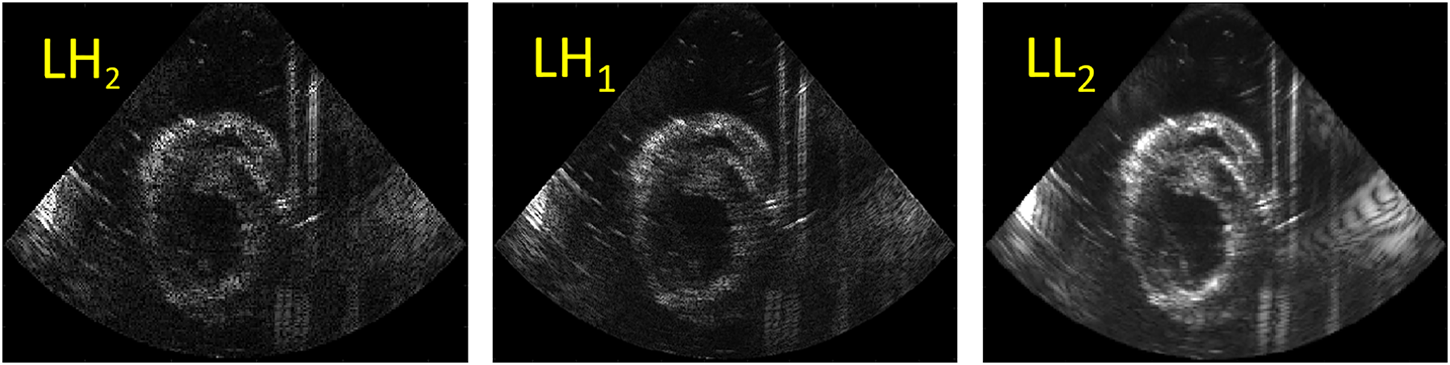

A fusion algorithm based on the discrete wavelet transform (DWT) was adapted to fuse the US images obtained from the two probes with different relative angles [33, 34]. The Haar wavelet is commonly used in image processing due to its fast and orthogonal properties [35–37]. It was selected to decompose the images into 2 layers with 7 subbands (see Figure 3). The fusion rules applied on DWT were defined as follows: for low frequency subband LL2 which encompasses the structures of the left ventricular wall, the maximum values of the two images were taken. High frequency subbands (LH, HL and HH) show small structures, e.g., the noise and speckles, in the US images. Hence, for these subbands, averaging was performed. Finally, after fusion, all the subbands were reconstructed into one fused image.

FIGURE 3

An example of DWT decomposition using 2 layers: the low horizontal and vertical high subbands (LH2, LH1) (left two images); the low frequency subband LL2 (right).